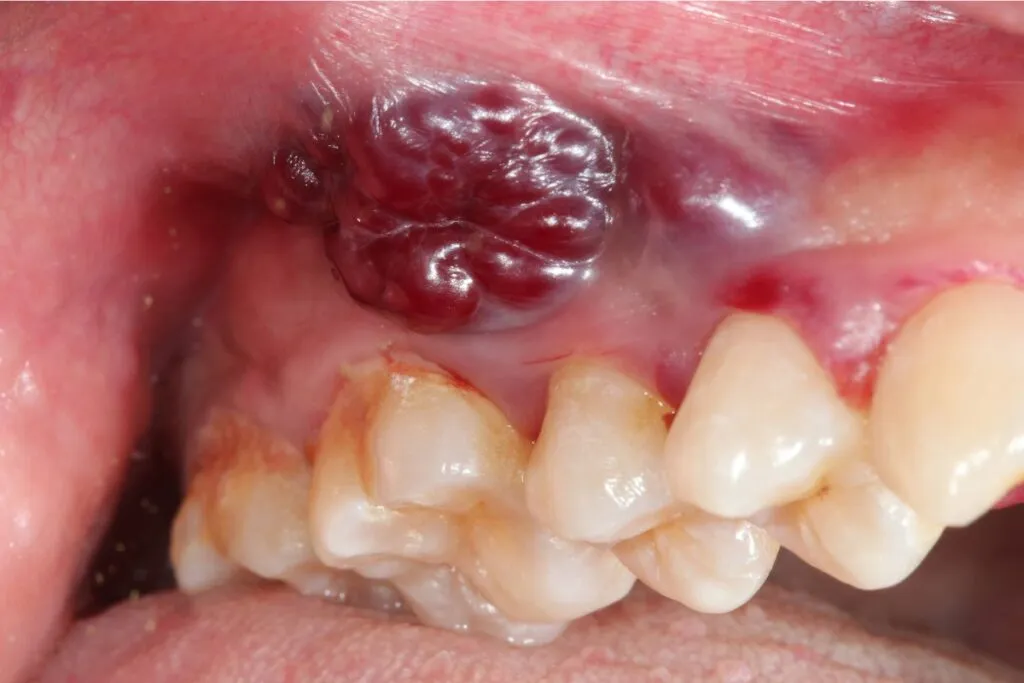

Guzek na dziąśle lub zgrubienie w policzku czy to powód do paniki?

Pojawienie się wyczuwalnego guzka lub zgrubienia na dziąśle, wewnętrznej stronie policzka, pod językiem lub w innej części jamy ustnej jest zdecydowanie sygnałem, który wymaga uwagi. Choć guzki mogą mieć różne przyczyny, w tym łagodne, nie należy ich bagatelizować, ponieważ mogą być wczesnym objawem nowotworu.